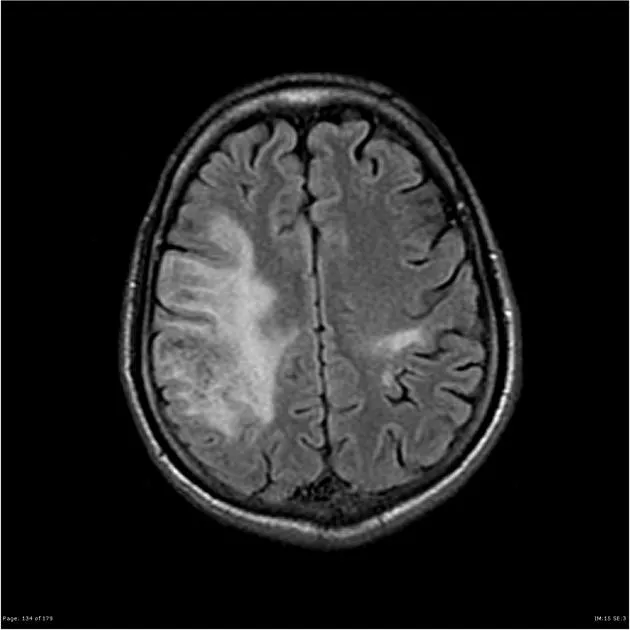

- Neurological signs/symptoms (focal deficit, seizure, altered consciousness)

- Precipitated by Valsalva (cough, sneeze = space-occupying lesion)